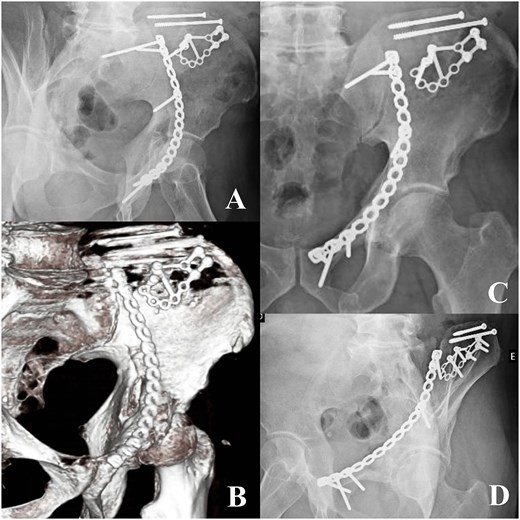

A 58-year-old male presented following a 3-meter fall, with an isolated ABC acetabular fracture of the right side (Fig. 1). Surgery was performed 2 days after the injury using an anterior pelvic approach via the Pfannenstiel incision combined with the first window of the ilioinguinal approach. Fixation began with the iliac crest using 4.5 mm cannulated screws to anchor the constant fragment, followed by a calcaneal plate to address comminution of the iliac wing, and a reconstruction plate for the anterior column (Fig. 2). As the posterior components were well-aligned post-fixation, a posterior approach was deemed unnecessary. Post-operative after 24 months radiographs and TC demonstrated anatomical reduction with no signs of implant failure (Fig. 3), just as shown in the TC comparison (Fig. 4). The physical exam presents a satisfactory range of motion (Fig. 5). Pain, function and quality of life outcomes were assessed using the Visual Analog Scale (VAS), Majeed Pelvic Score, and SF-12 up to 24 months post-operatively, respectively. The results are summarized in the following table (Table 1) and graphic (Fig. 6).

Radiographs 24 months postoperative (A, C, D) and CT 24 months (B).